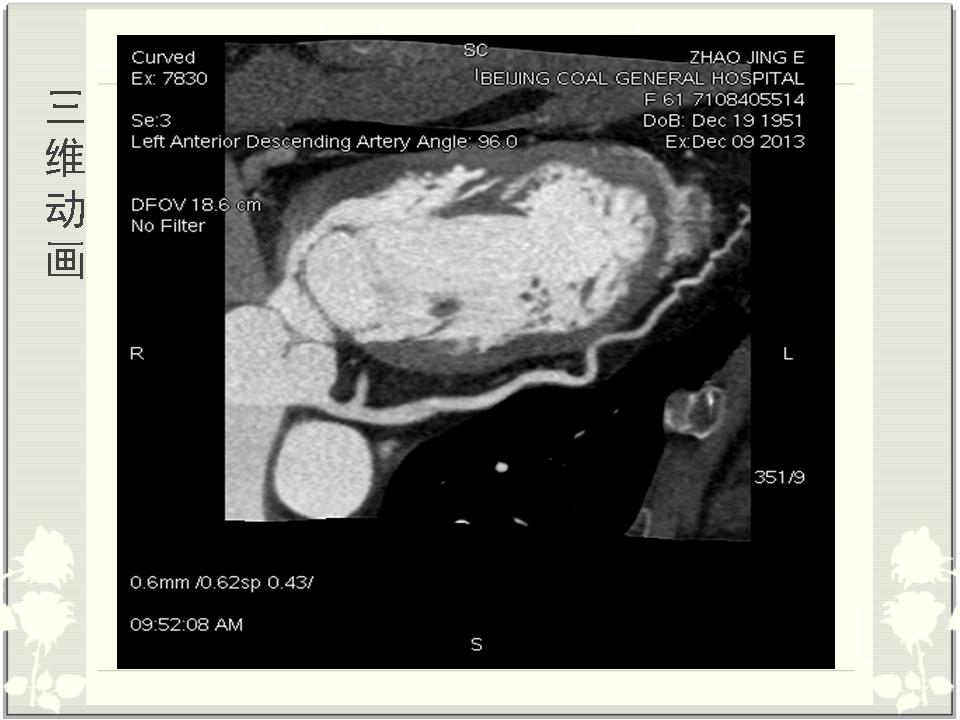

冠状动脉的解剖与CTA